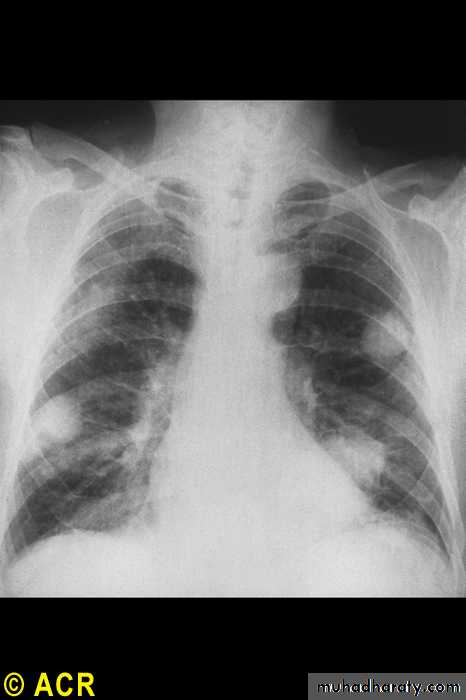

Pulmonary

NodulesPleural effusions

Fibrosing alveolitis

Bronchiolitis

Caplan's syndrome

Rheumatoid arthritis: pulmonary nodules